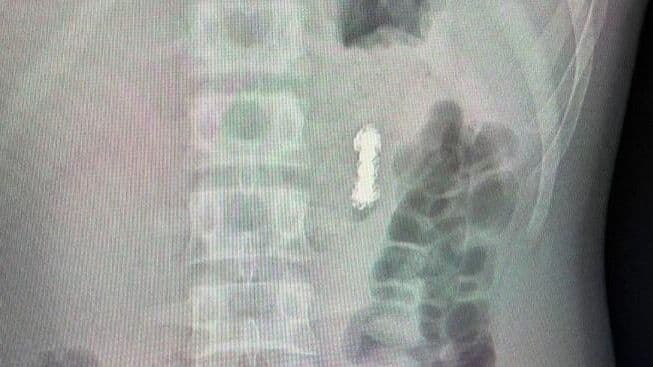

"Мы обнаружили семь магнитов в проекции желудка и еще четыре — в других отделах желудочно-кишечного тракта. За долгие годы они сцепились друг с другом, что привело к перфорации стенки желудка... Мальчику требовалась немедленное оперативное вмешательство: сначала мы извлекли семь магнитов из желудка, но оставшиеся четыре находились глубже по пищеварительному тракту, поэтому достать их эндоскопическим путем не удалось. Поэтому затем хирурги выполнили полостную операцию, в ходе которой извлекли оставшиеся четыре магнита в тонкой кишке", - сказал заведующий отделением эндоскопических методов диагностики и лечения Александр Иноземцев, слова которого приводятся в сообщении.